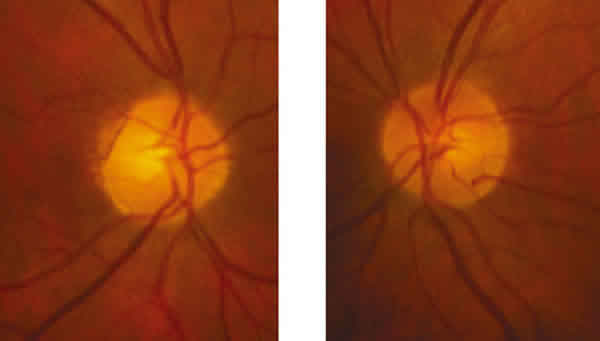

Fig. 2. Imagen de FO: la papila del OD muestra una muesca superior clara; en el OI muestra una muesca nasal inferior tenue que se corresponde con la llamada rodilla de Willbrandt.

La exploración se completa con un campo visual que revela la existencia de un defecto campimétrico superior e inferior en el OD (el tumor comprime el nervio óptico contra el hueso y daña las fibras superiores e inferiores). Además se aprecia un defecto en el campo visual contralateral, que es más difícil de entender. Es posible que se trate del llamado escotoma de la unión, y se debe a que tras decusarse las fibras nasales inferiores se introducen ligeramente en el nervio óptico contralateral, y por ello una lesión de la parte terminal del nervio óptico puede producir un defecto temporal superior en el ojo contralateral. A esta estructura anatómica se la denomina rodilla anterior de Willbrandt. Como puede apreciarse en las imágenes, el grado de concordancia entre el campo visual y la exploración papilar es muy alto. Se aprecia una muesca muy marcada en el reborde temporal superior de la papila derecha que se corresponde con el extenso defecto nasal inferior y otra menos marcada en la zona inferior que se corresponde con el defecto superior. En la papila izquierda se observa también una muesca nasal inferior que se corresponde con el defecto superior.